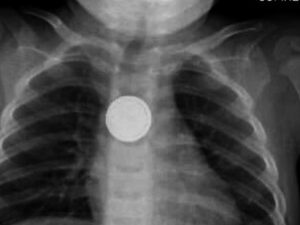

Deadly Button Batteries

කුඩා දරුවන් සිටින දෙමාපියන්ට සෞඛ්ය අංශවලින් හදිසි අනතුරු ඇඟවීමක්